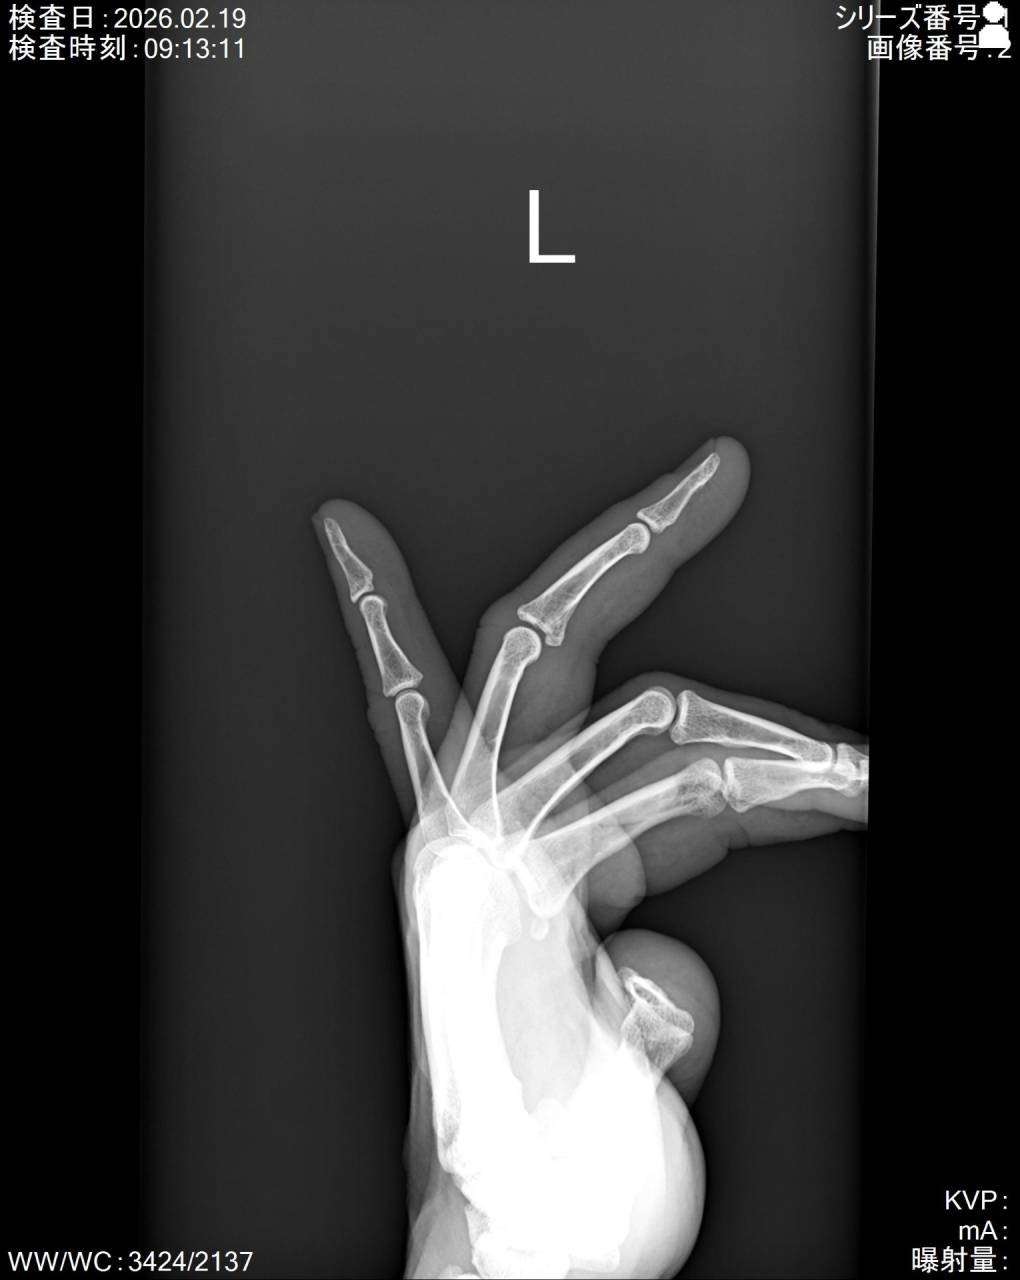

エコーで画像を確認すると中節骨基部に骨折線があり骨折の疑いがあったので当整骨院が提携している病院にてレントゲン検査を依頼し、撮影した画像を確認すると左第4指中節骨基部に骨折が確認できたので骨折として施術を行っていきます。